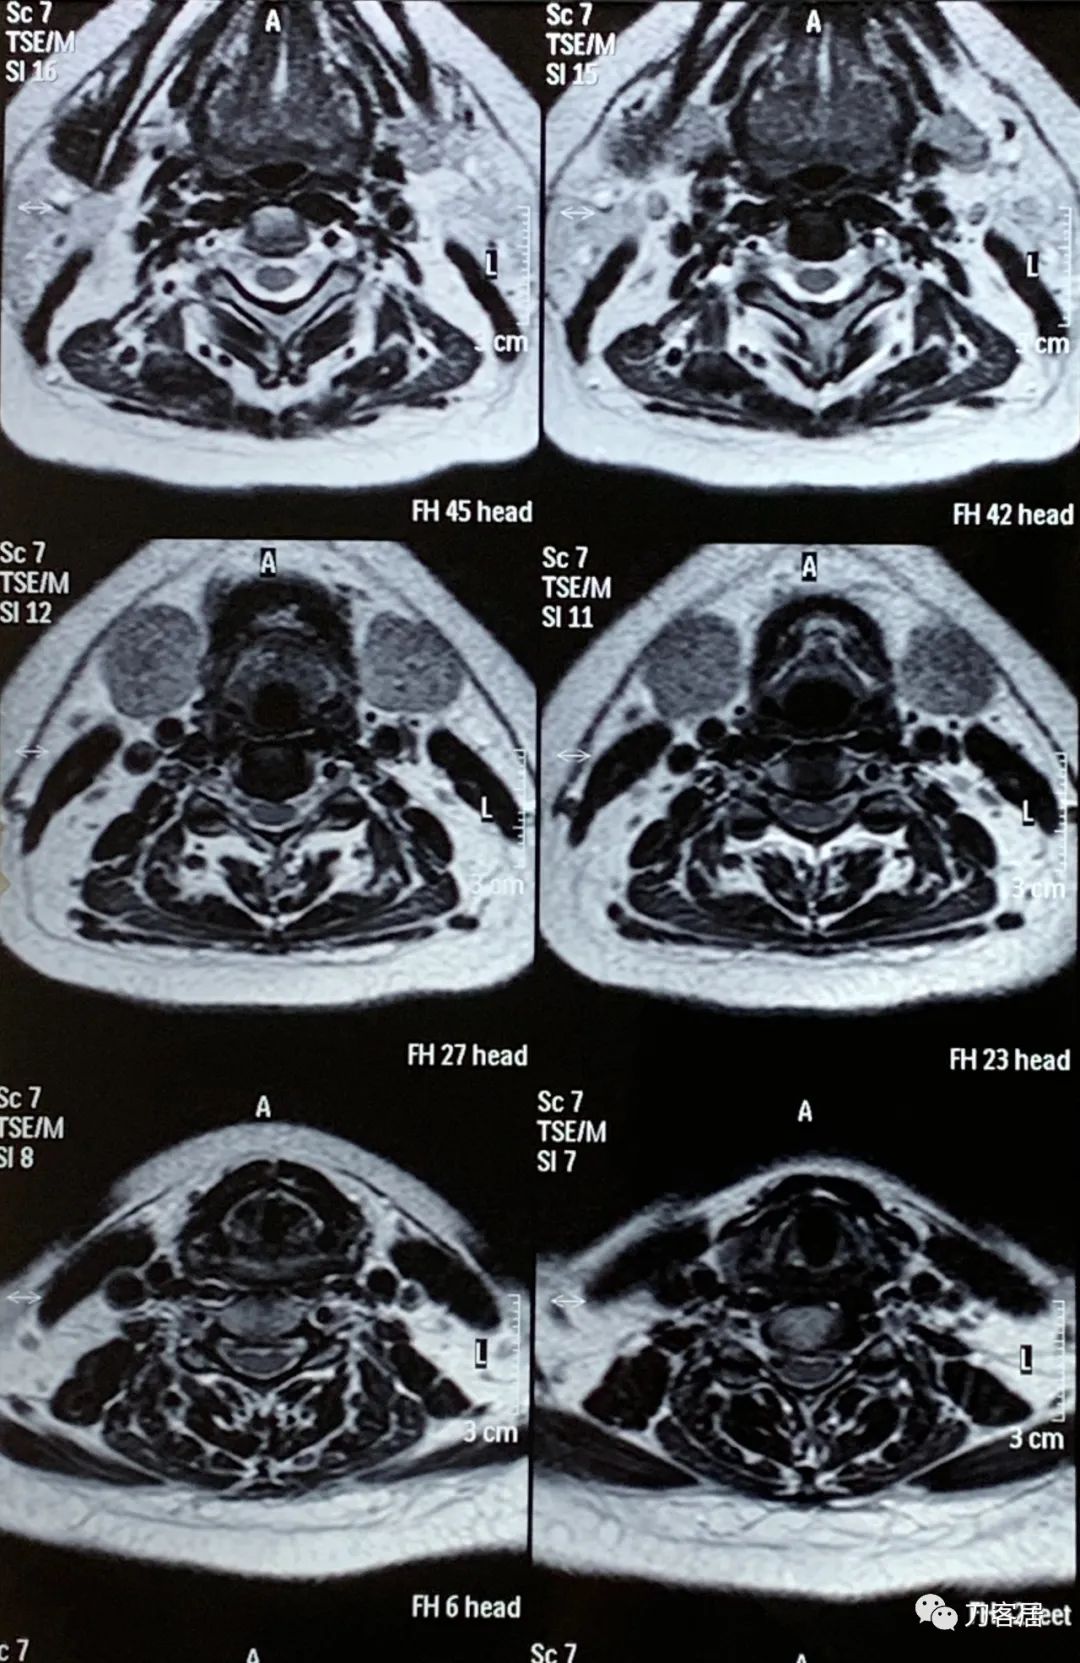

然后,2022年4月11日,患者又在当地另一家医院做了一次颈椎磁共振。

图27. 20220411平凉人民医院颈椎MRI01

图28. 20220411平凉人民医院颈椎MRI02

图29. 20220411平凉人民医院颈椎MRI03

图30. 20220411平凉人民医院颈椎MRI04

图31. 20220411平凉人民医院颈椎MRI05

图32. 20220411平凉人民颈椎MRI报告